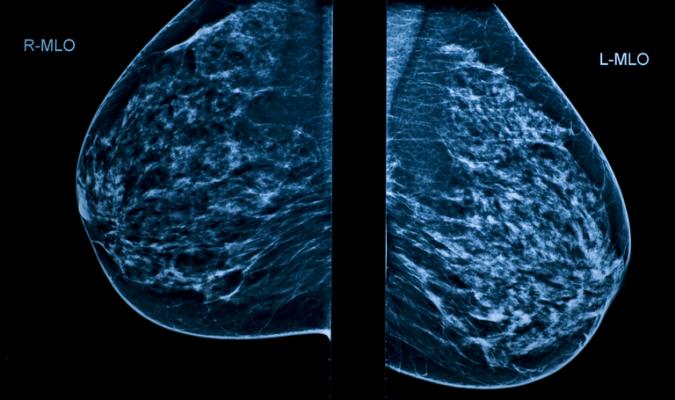

Breast cancer is a leading cause of death among women worldwide and many countries have introduced mammography screening programmes to detect and treat it early. But examining mammograms for early signs of cancer is high volume repetitive work for radiologists, and some cancers are missed.

Three large studies involving 79,910 women compared AI systems with the clinical decisions of the original radiologist. Of these, 1,878 had screen detected cancer or interval cancer (cancer diagnosed in-between routine screening appointments) within 12 months of screening.

The majority (34 out of 36 or 94%) of AI systems evaluated in these three studies were less accurate than a single radiologist, and all were less accurate than the consensus of two or more radiologists, which is the standard practice in Europe.